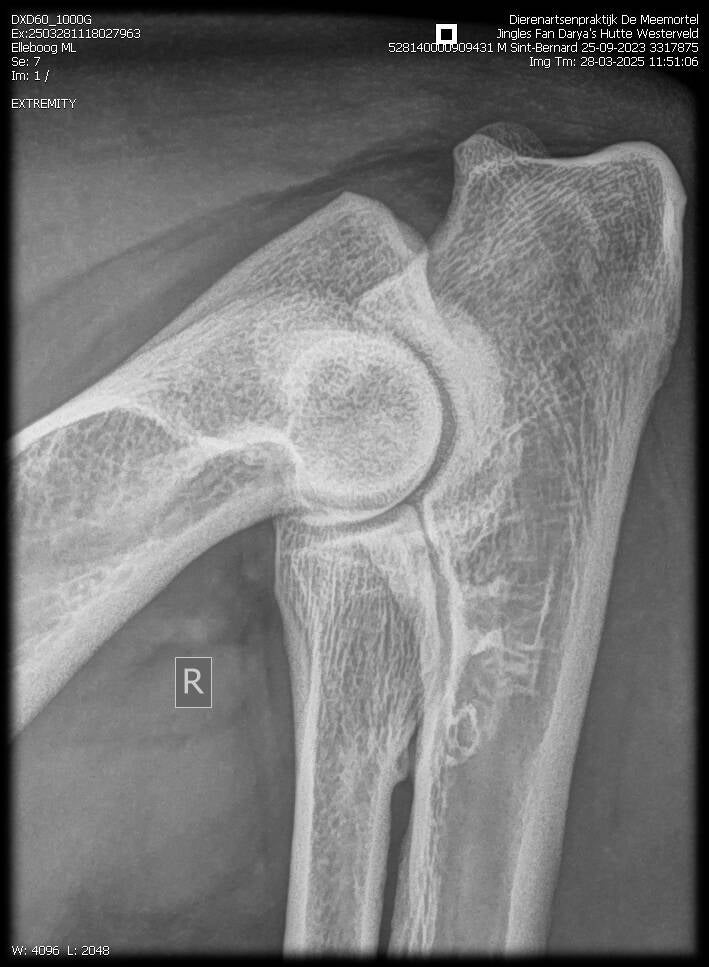

ELLEBOOGDYSPLASIE (ED)

Elleboogdysplasie (ED) is een verzamelnaam van vier verschillende aandoeningen van het ellebooggewricht, die allen op den duur tot deformatie en kreupelheid kunnen leiden. Het zijn ontwikkelingsstoornissen van met name het kraakbeen in de gewrichten die onder invloed van erfelijke en andere factoren ontstaan.

Sommige honden kunnen al op jonge leeftijd ernstige problemen hiervan ondervinden.

Net zoals bij HD kunnen uitsluitend röntgenfoto’s een optimaal beeld verschaffen over de toestand van de ellebooggewrichten.

De term elleboogdysplasie wordt gebruikt wanneer één of meer van de volgende aandoeningen in een ellebooggewricht aanwezig is.

OCD (Osteochondritis Dissecans), loslaten van een stukje kraakbeen van de bovenarm).

LPC (Los Processus Coronoideus, loslaten van een stukje van de ellepijp).

LPA (Los Processus Anconeus, loslaten van een stuk bot op een andere plaats van de ellepijp).

Incongruentie (een niet goed “passend” gewricht door een te lange of te korte ellepijp ten opzichte van het spaakbeen).

Ieder van bovengenoemde afwijkingen zal na enkele maanden leiden tot artrose.

ELBOW DYSPLASIA (ED)

Elbow dysplasia (ED) is a collective term for four different conditions affecting the elbow joint, all of which can eventually lead to deformation and lameness. These are developmental disorders, particularly of the cartilage in the joints, which arise under the influence of hereditary and other factors.

Some dogs can experience serious problems with this at a young age.

As with HD, only X-rays can provide an optimal picture of the condition of the elbow joints.

The term elbow dysplasia is used when one or more of the following conditions are present in an elbow joint.

OCD (Osteochondritis Dissecans), detachment of a piece of cartilage from the upper arm.

LPC (Loose Coronoid Process, detachment of a piece of the ulna).

LPA (Loose Anconeus Process, detachment of a piece of bone in another part of the ulna).

Incongruence (a joint that does not fit properly due to the ulna being too long or too short in relation to the radius).

Each of the above abnormalities will lead to osteoarthritis after a few months.

Osteoarthritis refers to changes in a joint (bone reactions) that can occur during the course of the disease process, which are permanent and mainly characterized by initial pain (limping just after getting up), “walking through it” (i.e., walking better after some time) and a relapse after a lot of exertion.

Röntgenfoto's Elvis